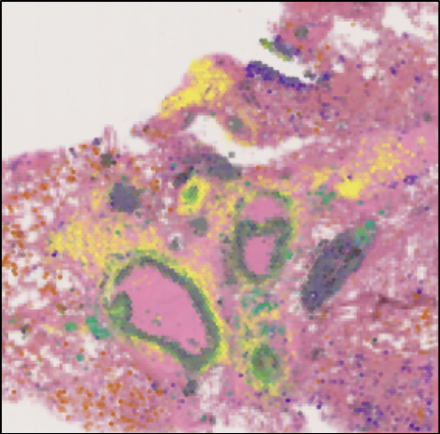

With separate funding from Wellcome LEAP, Dr Omer Bayraktar’s team has also established a collaboration with researchers at the Africa Health Research Institute in South Africa to study lung granulomas – an area of tightly packed immune and diseased lung cells in individuals infected with tuberculosis (TB).

This work, led by Senior Staff Scientist Dr Fani Memi, uses spatial technology to profile granulomas and the surrounding lung tissue changes that cause functional impairment, in order to understand and predict transitions between different TB disease states. To date, we still do not understand what determines whether granulomas resolve, progress or disseminate; therefore, this work will shed more light on the evolution of granulomas and our overall understanding of disease progression.

One of the initial challenges the team has faced is in relation to the samples. The tissue they received for the project was quite old and had not been optimally prepared and stored for spatial – most spatial technologies work best with fresh frozen tissue, whereas these tissues had been stored in formalin for many years. Despite this challenge, Fani and the team ran several pilot tests to optimise the protocol and eventually were able to detect TB genes for the first time, as well as increase overall sensitivity of gene detection.

The team’s initial results point at a surprising degree of spatial organisation in the granulomas. Currently, Fani and the team are trying to see if granuloma spatial architecture changes across different stages of tuberculosis infection.

A particular interest of the teams is the intriguing similarities between tumours and granulomas in the way they manipulate the immune system to their benefit. Comparing their respective spatially complex cellular microenvironments might reveal common principles of chronic tissue responses and immune-pathogen/immune-tumour interactions.

Representative image of a large airway with extensive inflammation, possible early stage granulomas, mucus and debris. 17-plex Immuno-Oncology biomarkers of alveolar airways from Cystic Fibrosis lung tissue, acquired on the RareCyte Orion Spatial Biology platform.